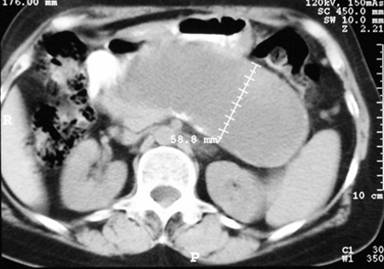

A 67-year-old woman was referred to our department with the presence of an abdominal mass in the upper abdomen, detected during a routine gynecologic visit. She had had an episode of acute pancreatitis 9 years earlier, with the subsequent development of a pancreatic pseudocyst, which was surgically managed by a cystogastrostomy 2 months later in another institution; a cholecystectomy was performed as well. She denied any episode of abdominal pain thereafter and did not recall post-surgical follow-up beyond one year. There was no history, or clinical nor laboratory data of diabetes or exocrine pancreatic insufficiency. Physical examination revealed a midline surgical scar, minimal tenderness upon palpation of a non-mobile mass in the upper abdomen. Laboratory serum results showed no abnormalities. The abdominal computed tomography (CT) scan revealed a 135x58 mm well-circumscribed unilocular cystic lesion in the region of the pancreas (Figure 1).

Figure 1. CT scan showing a well-circumscribed unilocular pancreatic pseudocyst in close apposition to the posterior gastric wall. |